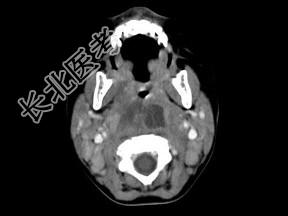

- 多项选择题10个月大的婴儿,发热, 曾患中耳炎,CT扫描如图所示, 正确的描述或诊断是 ( )

A、咽后壁软组织肿胀

B、其内密度不均

C、颈椎骨质未见明显异常

D、咽后壁脓肿

E、咽后壁寒性脓肿